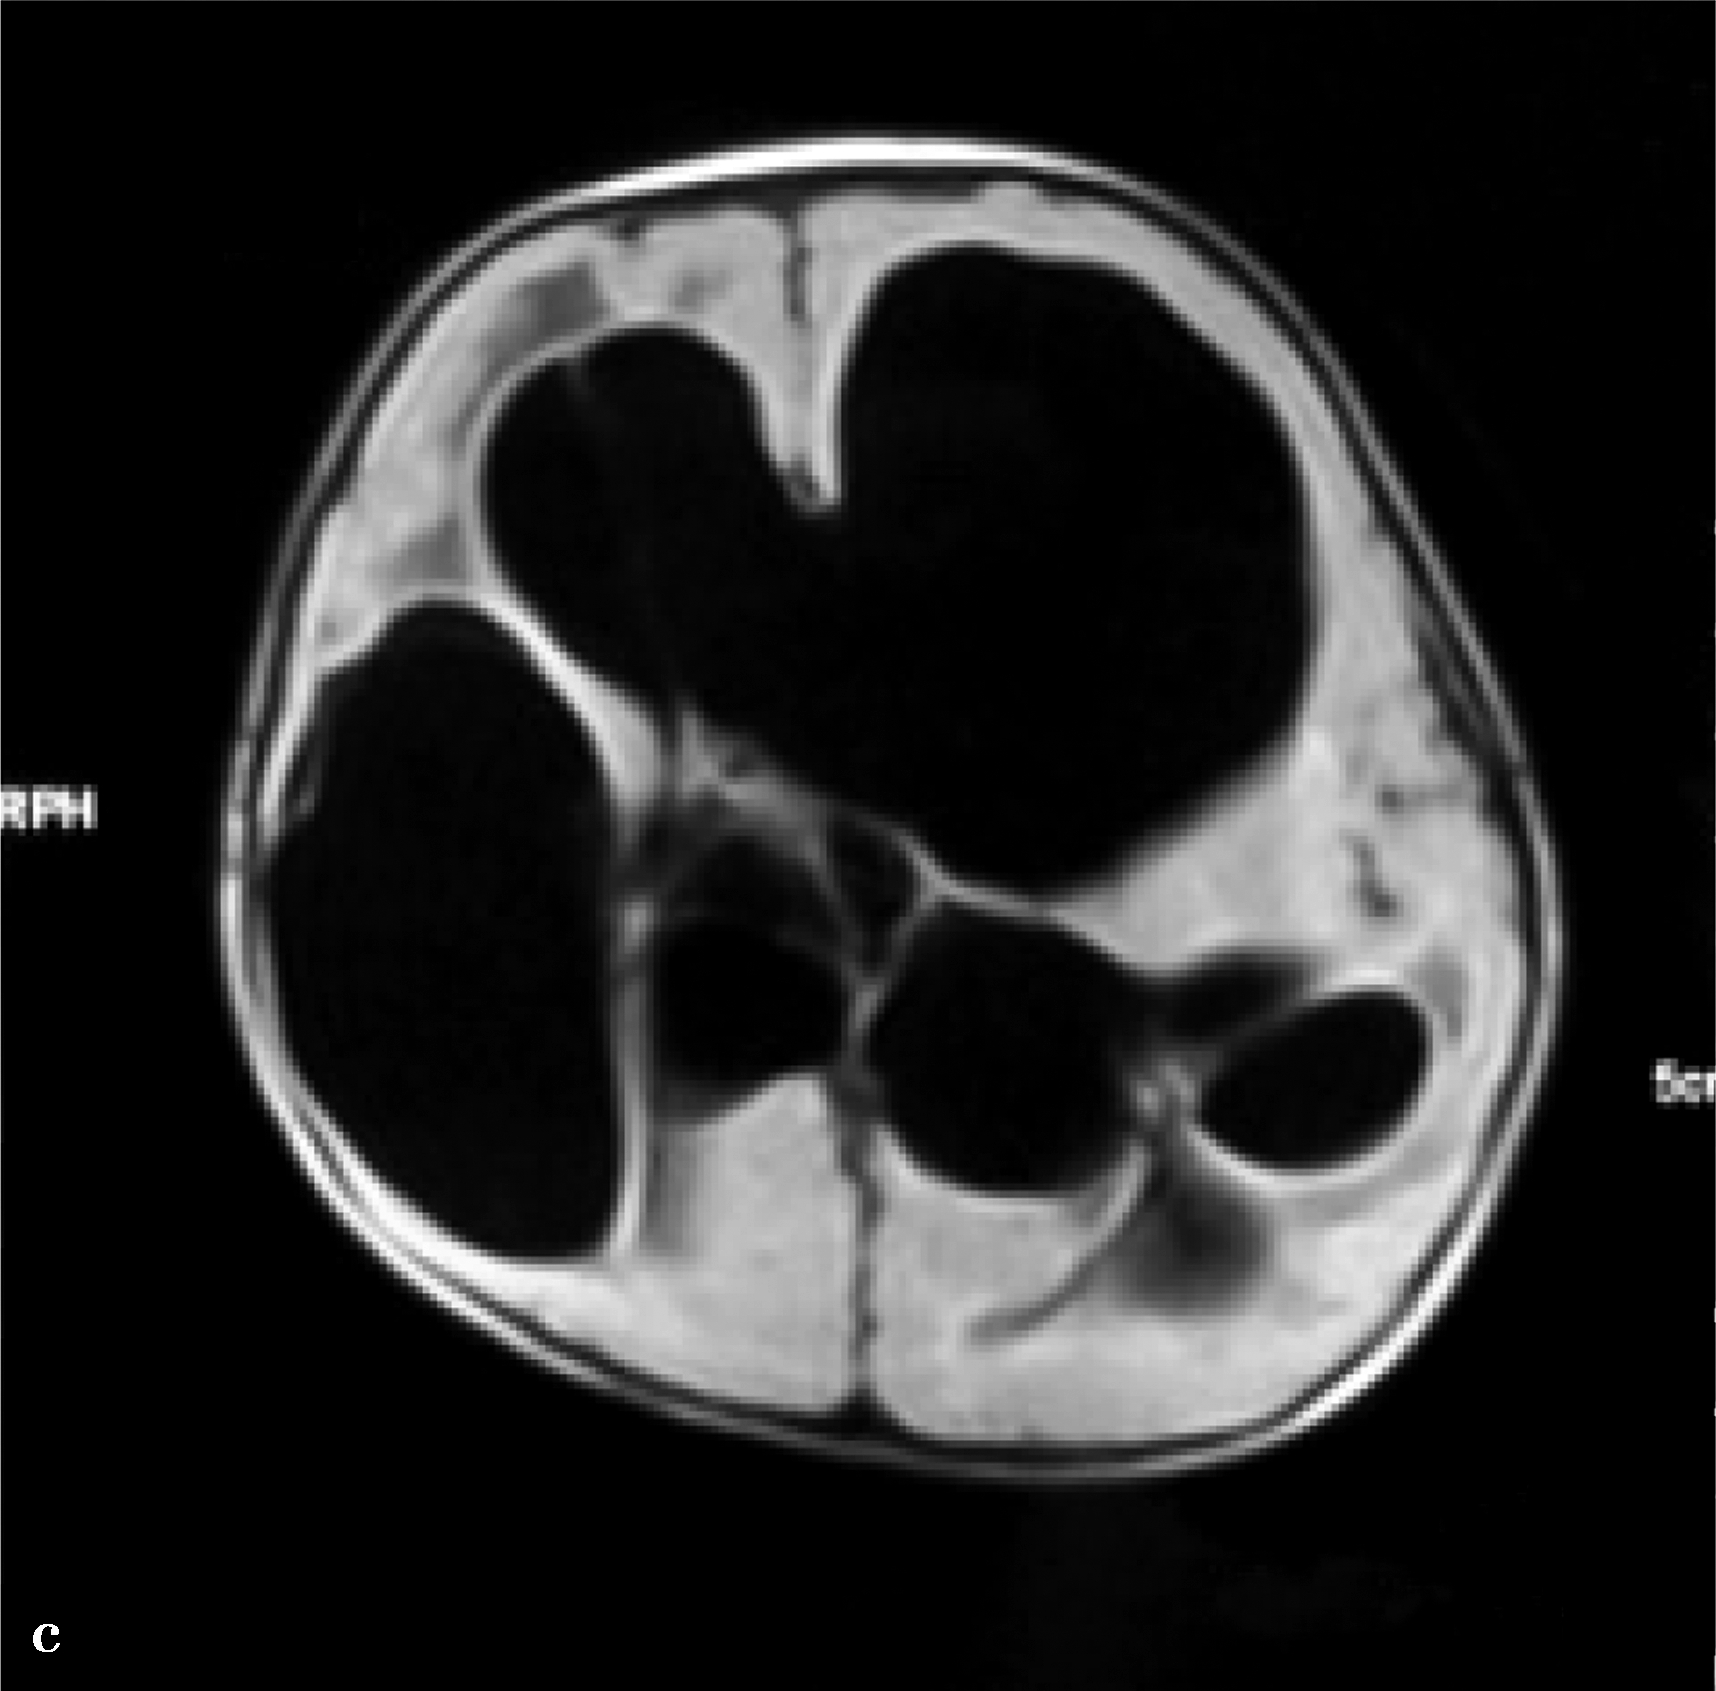

图3-1-4-7 孤立脑室

a.MRI显示孤立第三脑室;b.CT显示幕上脑室裂隙样,孤立第四脑室;c.双侧脑室分流术后,双侧脑室颞角孤立,第四脑室孤立;d.孤立第三脑室与孤立第四脑室同时存在